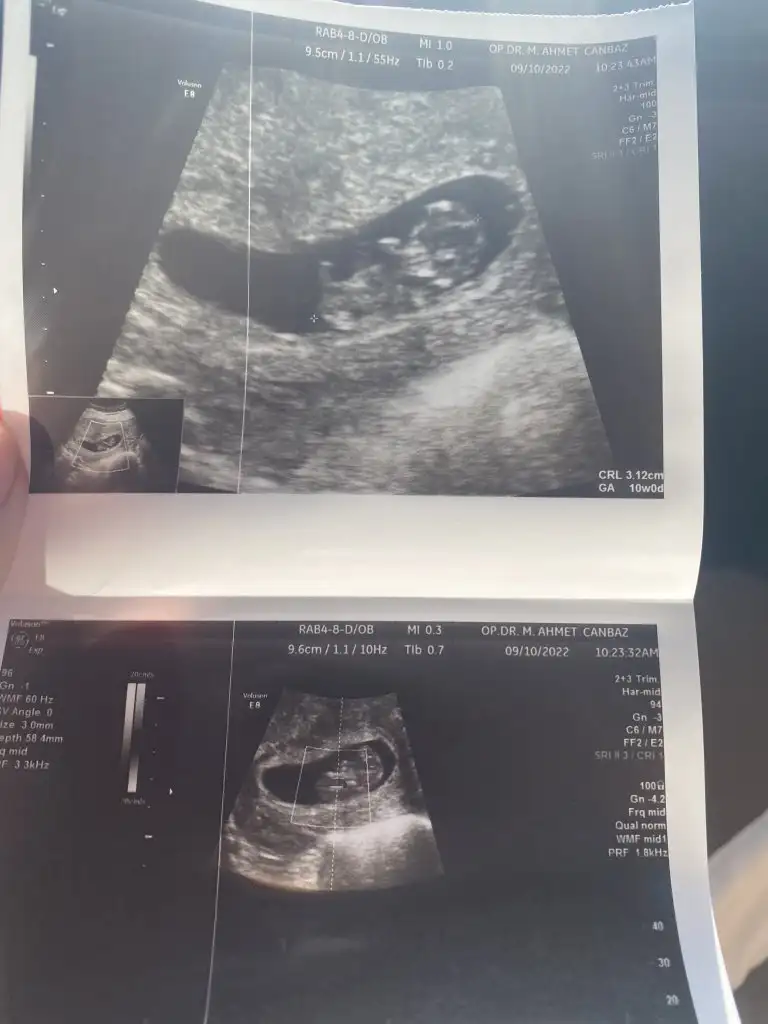

Merhabalar bu 6+4 fotografım buda 10 haftalım😊